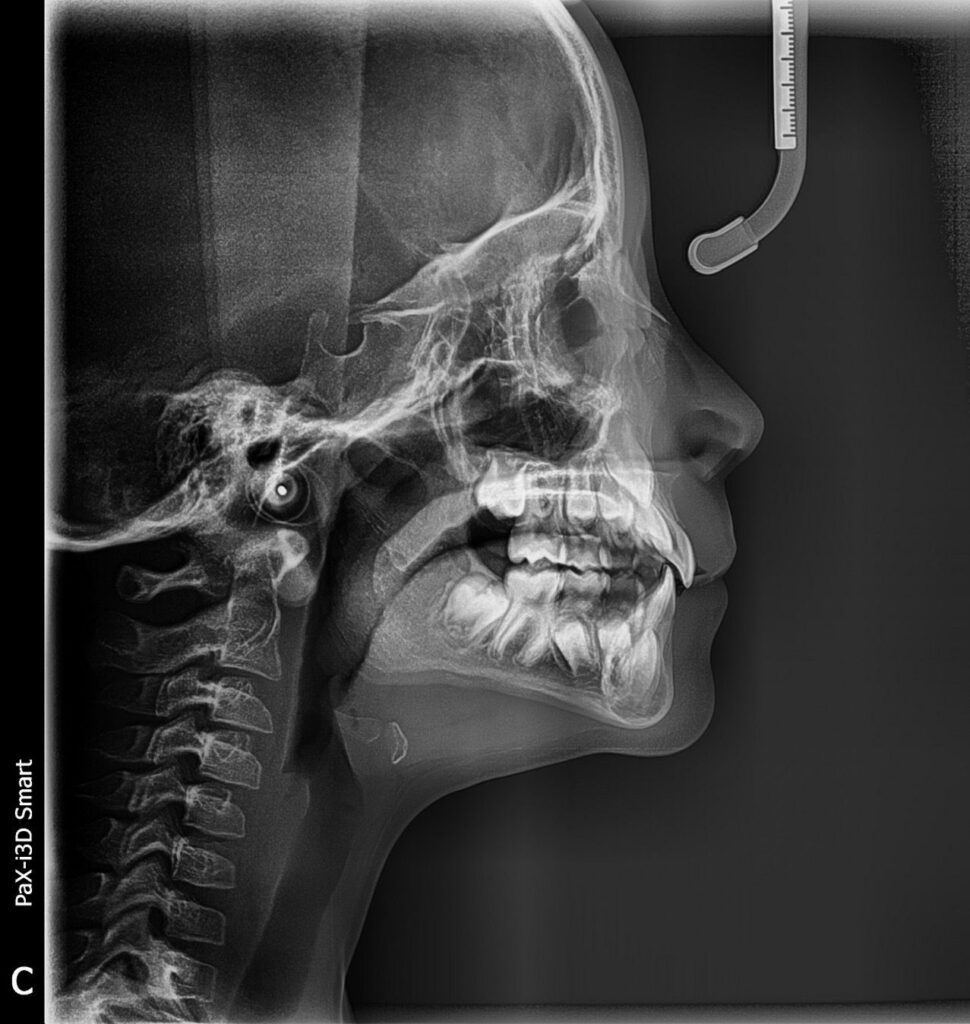

Raio-x Panorâmico e teleradiografia

Telerradiografia lateral analisa o perfil ósseo facial e o posicionamento dos dentes, auxiliando no diagnóstico e planejamento ortodôntico